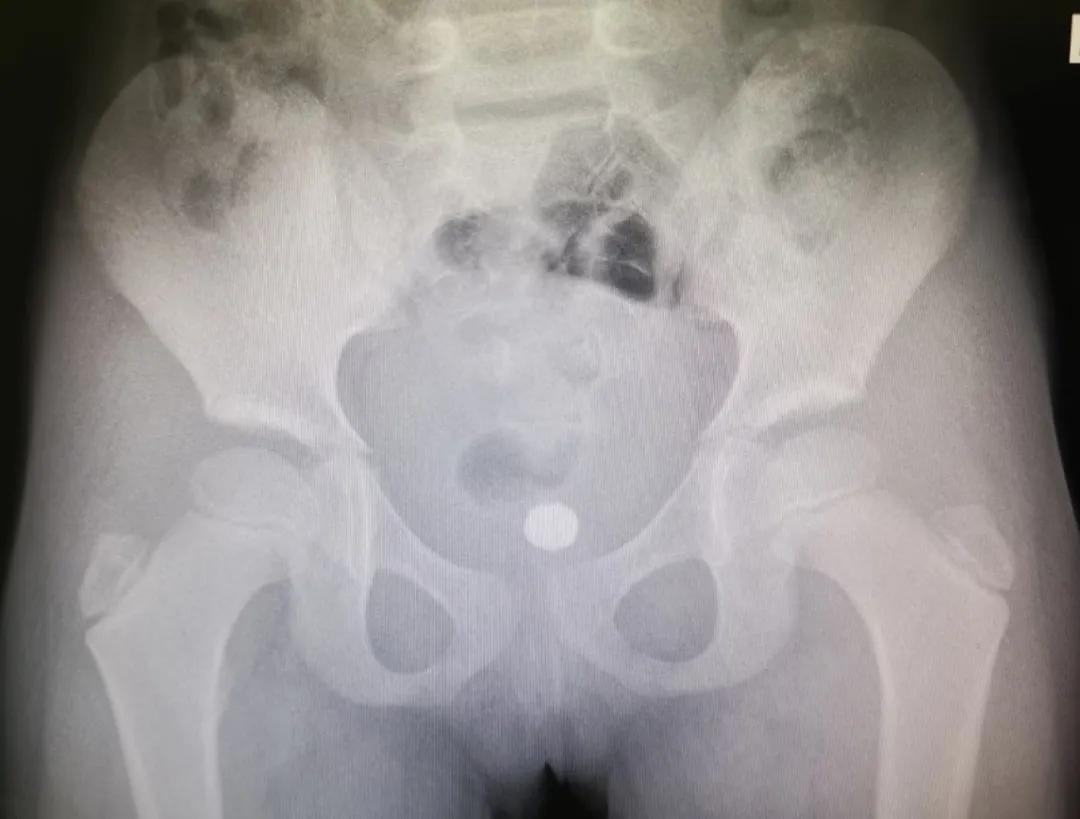

据悉,孩子今年四岁,事发当日下午穿着开裆裤在家中玩耍,因好奇将1枚2-3cm玻璃弹珠小丁丁塞入包皮。孩子当时觉得好玩,接着又塞了1颗。

不久,包皮开始出现红肿疼痛,但仍能自主排尿。此时,家长也终于发现了异常,孩子的小丁丁有明显的两块凸起。经过再三询问,又查看了周围的环境和玩具,才知道孩子把两个玻璃珠塞进去了。

患儿晚上七点多被送至南京市儿童医院,泌尿外科汪俊主治医师立即安排了急诊手术。“幸好玻璃珠并没有进入尿道和膀胱,只是被塞进了*头龟**和包皮之间,包皮水肿造成异物嵌顿,只需将水肿的包皮切开,就可以取出珠子。”

在和家属的充分沟通后,同时行包皮环切术。手术非常成功,两颗玻璃珠被顺利取出,术后也没有感染和肿胀。